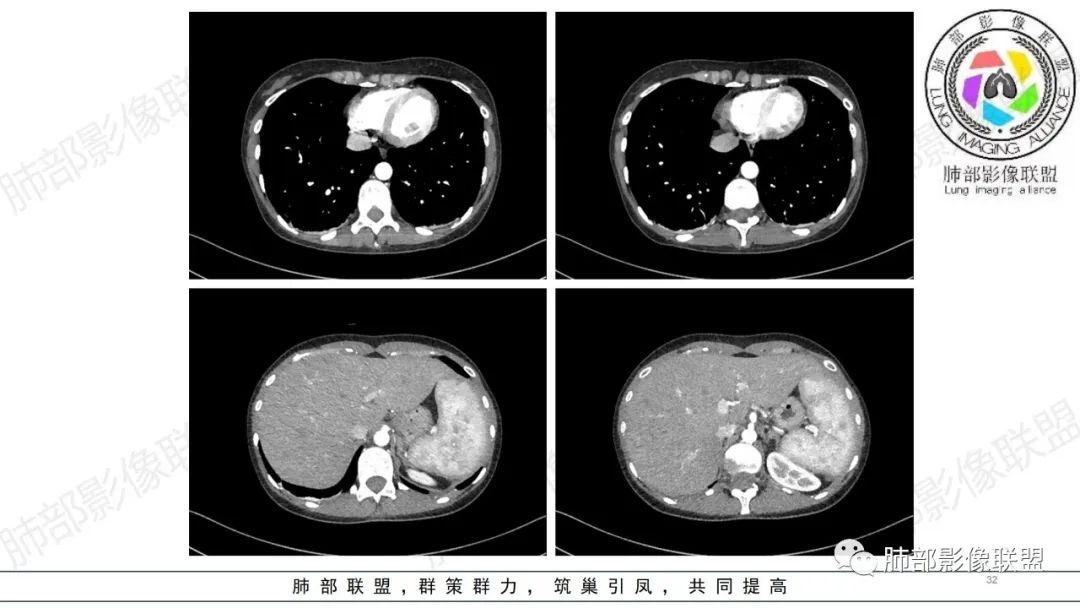

【病例】肺部弥漫大B淋巴瘤病例思考及启示

肺内气腔磨玻璃结节,肝脾肿大,治疗后间质改变,弥漫大B可能

34岁女性患者,“哮喘”病史30年,近期有可疑刺激性气体吸入史;因乏力半年,咳嗽、憋气、发热4天就诊;6.1CT提示双肺广泛毛玻璃影及粟粒样结节,胸膜下闲置及血管周闲置,可见树丫征,部分小叶间隔增厚。考虑:1.过敏性肺泡炎,有可疑刺激气体接触史,胸膜下闲置,广泛毛玻璃影,地图样分布,粟粒结节边界模糊,支持过敏性肺泡炎,但糖皮激素治疗效果不佳,且动态复查血常规血红蛋白进行性降低,过敏性肺泡炎 不符合;2.肺含铁血黄素沉积症:患者30“哮喘”病史,可能为肺含铁症状,肺部CT提示双肺弥漫毛玻璃影及粟粒结节影,中下肺明显,肺底部分小叶间隔增厚,近期咳嗽、憋气、发热,血常规血红蛋白进行性下降,考虑肺含铁急性期症状,但临床无咯血症状,肺含铁不典型。综合考虑:肺含铁血黄素沉积症>过敏性肺泡炎。